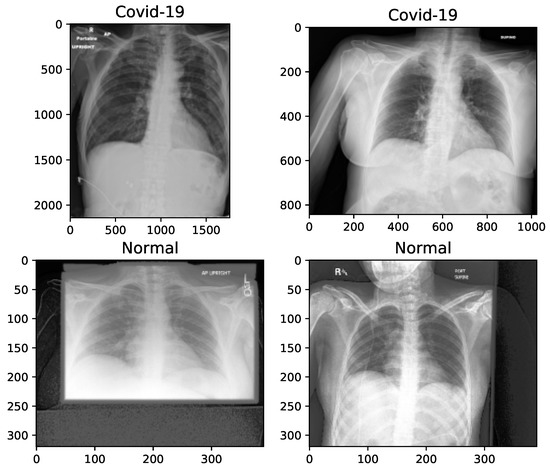

The key problem with small and unbalanced datasets is that models trained with them may not be generalized. Hence, these models suffer the issue of overfitting. Data augmentation is an approach to reducing overfitting, by which we are able to increase the amount of data, with only using available data [61]. In this paper, 100 images, with an equal proportion of classes, is held out for testing the model, and the number of samples of each class is balanced by increasing the number of COVID-19 chest X-rays to 500 images. The augmented images are randomly selected from the original X-rays. In total, 1000 (500 normal + 500 COVID-19) images are employed for the training phase. On the other hand, image preprocessing is needed, because the images are not of the same size, as shown in Figure 1, and therefore are converted into the same size for training. In Table 1, we present the manipulations that are applied to the X-rays, before proceeding with the augmentation.

For this purpose, we have used the “Augmentor”—a Python package designed to aid the augmentation and artificial generation of image data for machine learning tasks. It is primarily a data augmentation tool, but also incorporate basic image preprocessing functionality. It has an emphasis on providing operations that are typically used in the generation of image data for machine learning problems. The visualization of X-ray images of each class, after manipulation, is shown in Figure 2.

Figure 2. X-ray image samples of two categories after image manipulation.